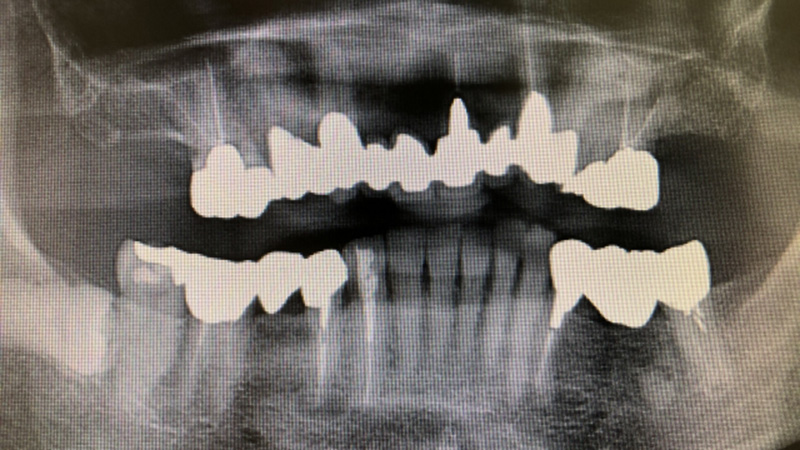

歯の後遺障害 とは、一定数以上の歯に歯科補綴(しかほてつ)を加えたものです。

補綴とは、歯が喪失したり、欠損した場合に、クラウン(歯全体を覆う被せ物)や入れ歯などの人工物で補うことです。

歯の後遺障害認定基準は次の通りです。

| 10級4号 | 14歯以上に対し歯科補綴を加えたもの |

| 11級4号 | 10歯以上に対し歯科補綴を加えたもの |

| 12級3号 | 7歯以上に対し歯科補綴を加えたもの |

| 13級5号 | 5歯以上に対し歯科補綴を加えたもの |

| 14級2号 | 3歯以上に対し歯科補綴を加えたもの |